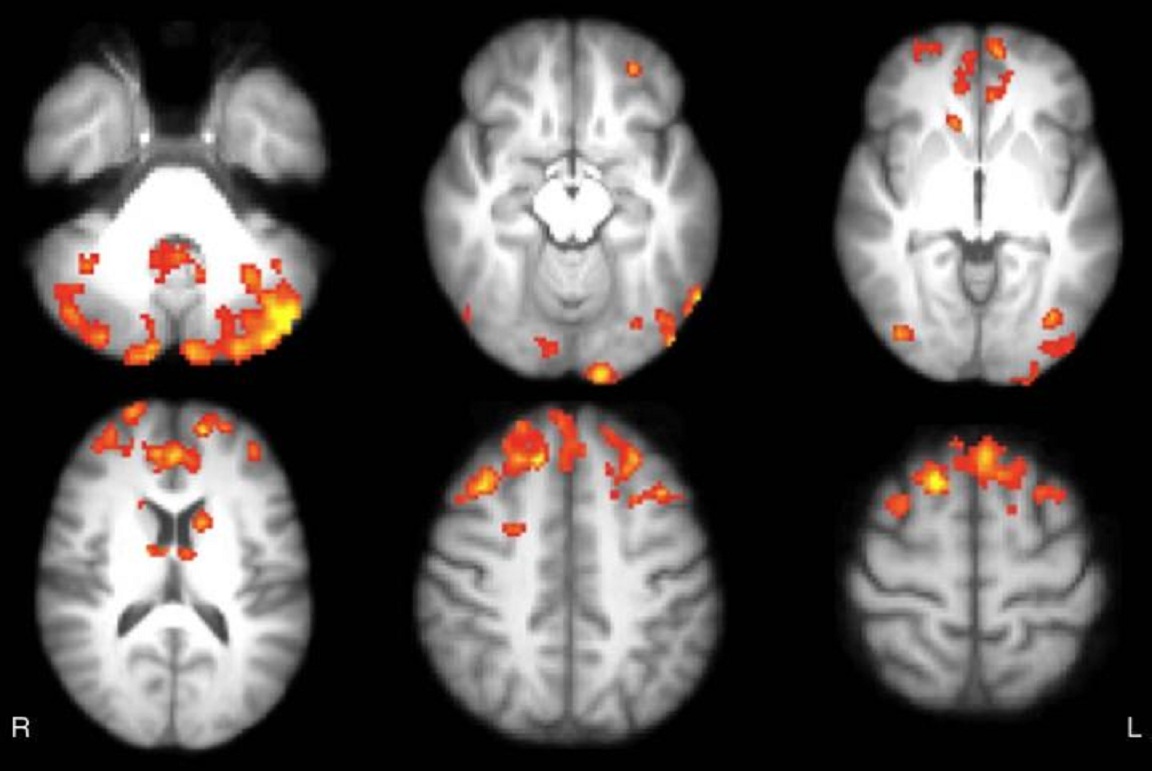

Mapas estadísticos axiales muestran las áreas de reducción de la conectividad funcional en el tálamo de pacientes con EM, en comparación los sujetos sanos. Los pacientes mostraron significativamente menor conectividad funcional en cerebelo, cortezas frontal y occipital, núcleo caudado ytálamo, de forma bilateral. Fuente: Radiological Society of North America.

Los participantes fueron evaluados, mediante pruebas cognitivas y por resonancia magnética (RM) de 3-Tesla con el cerebro en estado de reposo, al inicio del estudio y después del período de ocho semanas. Las imágenes de la RM cuando el cerebro está en estado de reposo, o cuando no se centra en una tarea en particular, proporcionan información importante sobre la conectividad neuronal.

“La RM te permite estudiar qué áreas del cerebro están activas simultáneamente, y da información sobre la participación de ciertas áreas del cerebro con circuitos específicos”, explica De Giglio en un comunicado de la RSNA. “Cuando hablamos de una mayor conectividad, nos referimos a que estos circuitos se han modificado, aumentando la extensión de las áreas que funcionan al mismo tiempo”.

Los participantes fueron evaluados, mediante pruebas cognitivas y por resonancia magnética (RM) de 3-Tesla con el cerebro en estado de reposo, al inicio del estudio y después del período de ocho semanas. Las imágenes de la RM cuando el cerebro está en estado de reposo, o cuando no se centra en una tarea en particular, proporcionan información importante sobre la conectividad neuronal.

“La RM te permite estudiar qué áreas del cerebro están activas simultáneamente, y da información sobre la participación de ciertas áreas del cerebro con circuitos específicos”, explica De Giglio en un comunicado de la RSNA. “Cuando hablamos de una mayor conectividad, nos referimos a que estos circuitos se han modificado, aumentando la extensión de las áreas que funcionan al mismo tiempo”.

Tras el seguimiento realizado a los 12 pacientes que jugaron a videojuegos se constató en estos un aumento significativo de la conectividad funcional del tálamo, en áreas del cerebro que constituyen una de las redes cerebrales más importantes para la cognición. Estos resultados, afirman los investigadores, proporcionan un ejemplo de la plasticidad del cerebro, que es la capacidad que este órgano tiene para formar nuevas conexiones a lo largo de la vida.

Las modificaciones en la conectividad funcional que se mostraron tras el entrenamiento con videojuegos se correspondieron con mejoras significativas en puntuaciones de pruebas que evaluaban la atención sostenida y la función ejecutiva, que son habilidades cognitivas de nivel superior que nos ayudan a organizar nuestras vidas y a regular nuestro comportamiento.